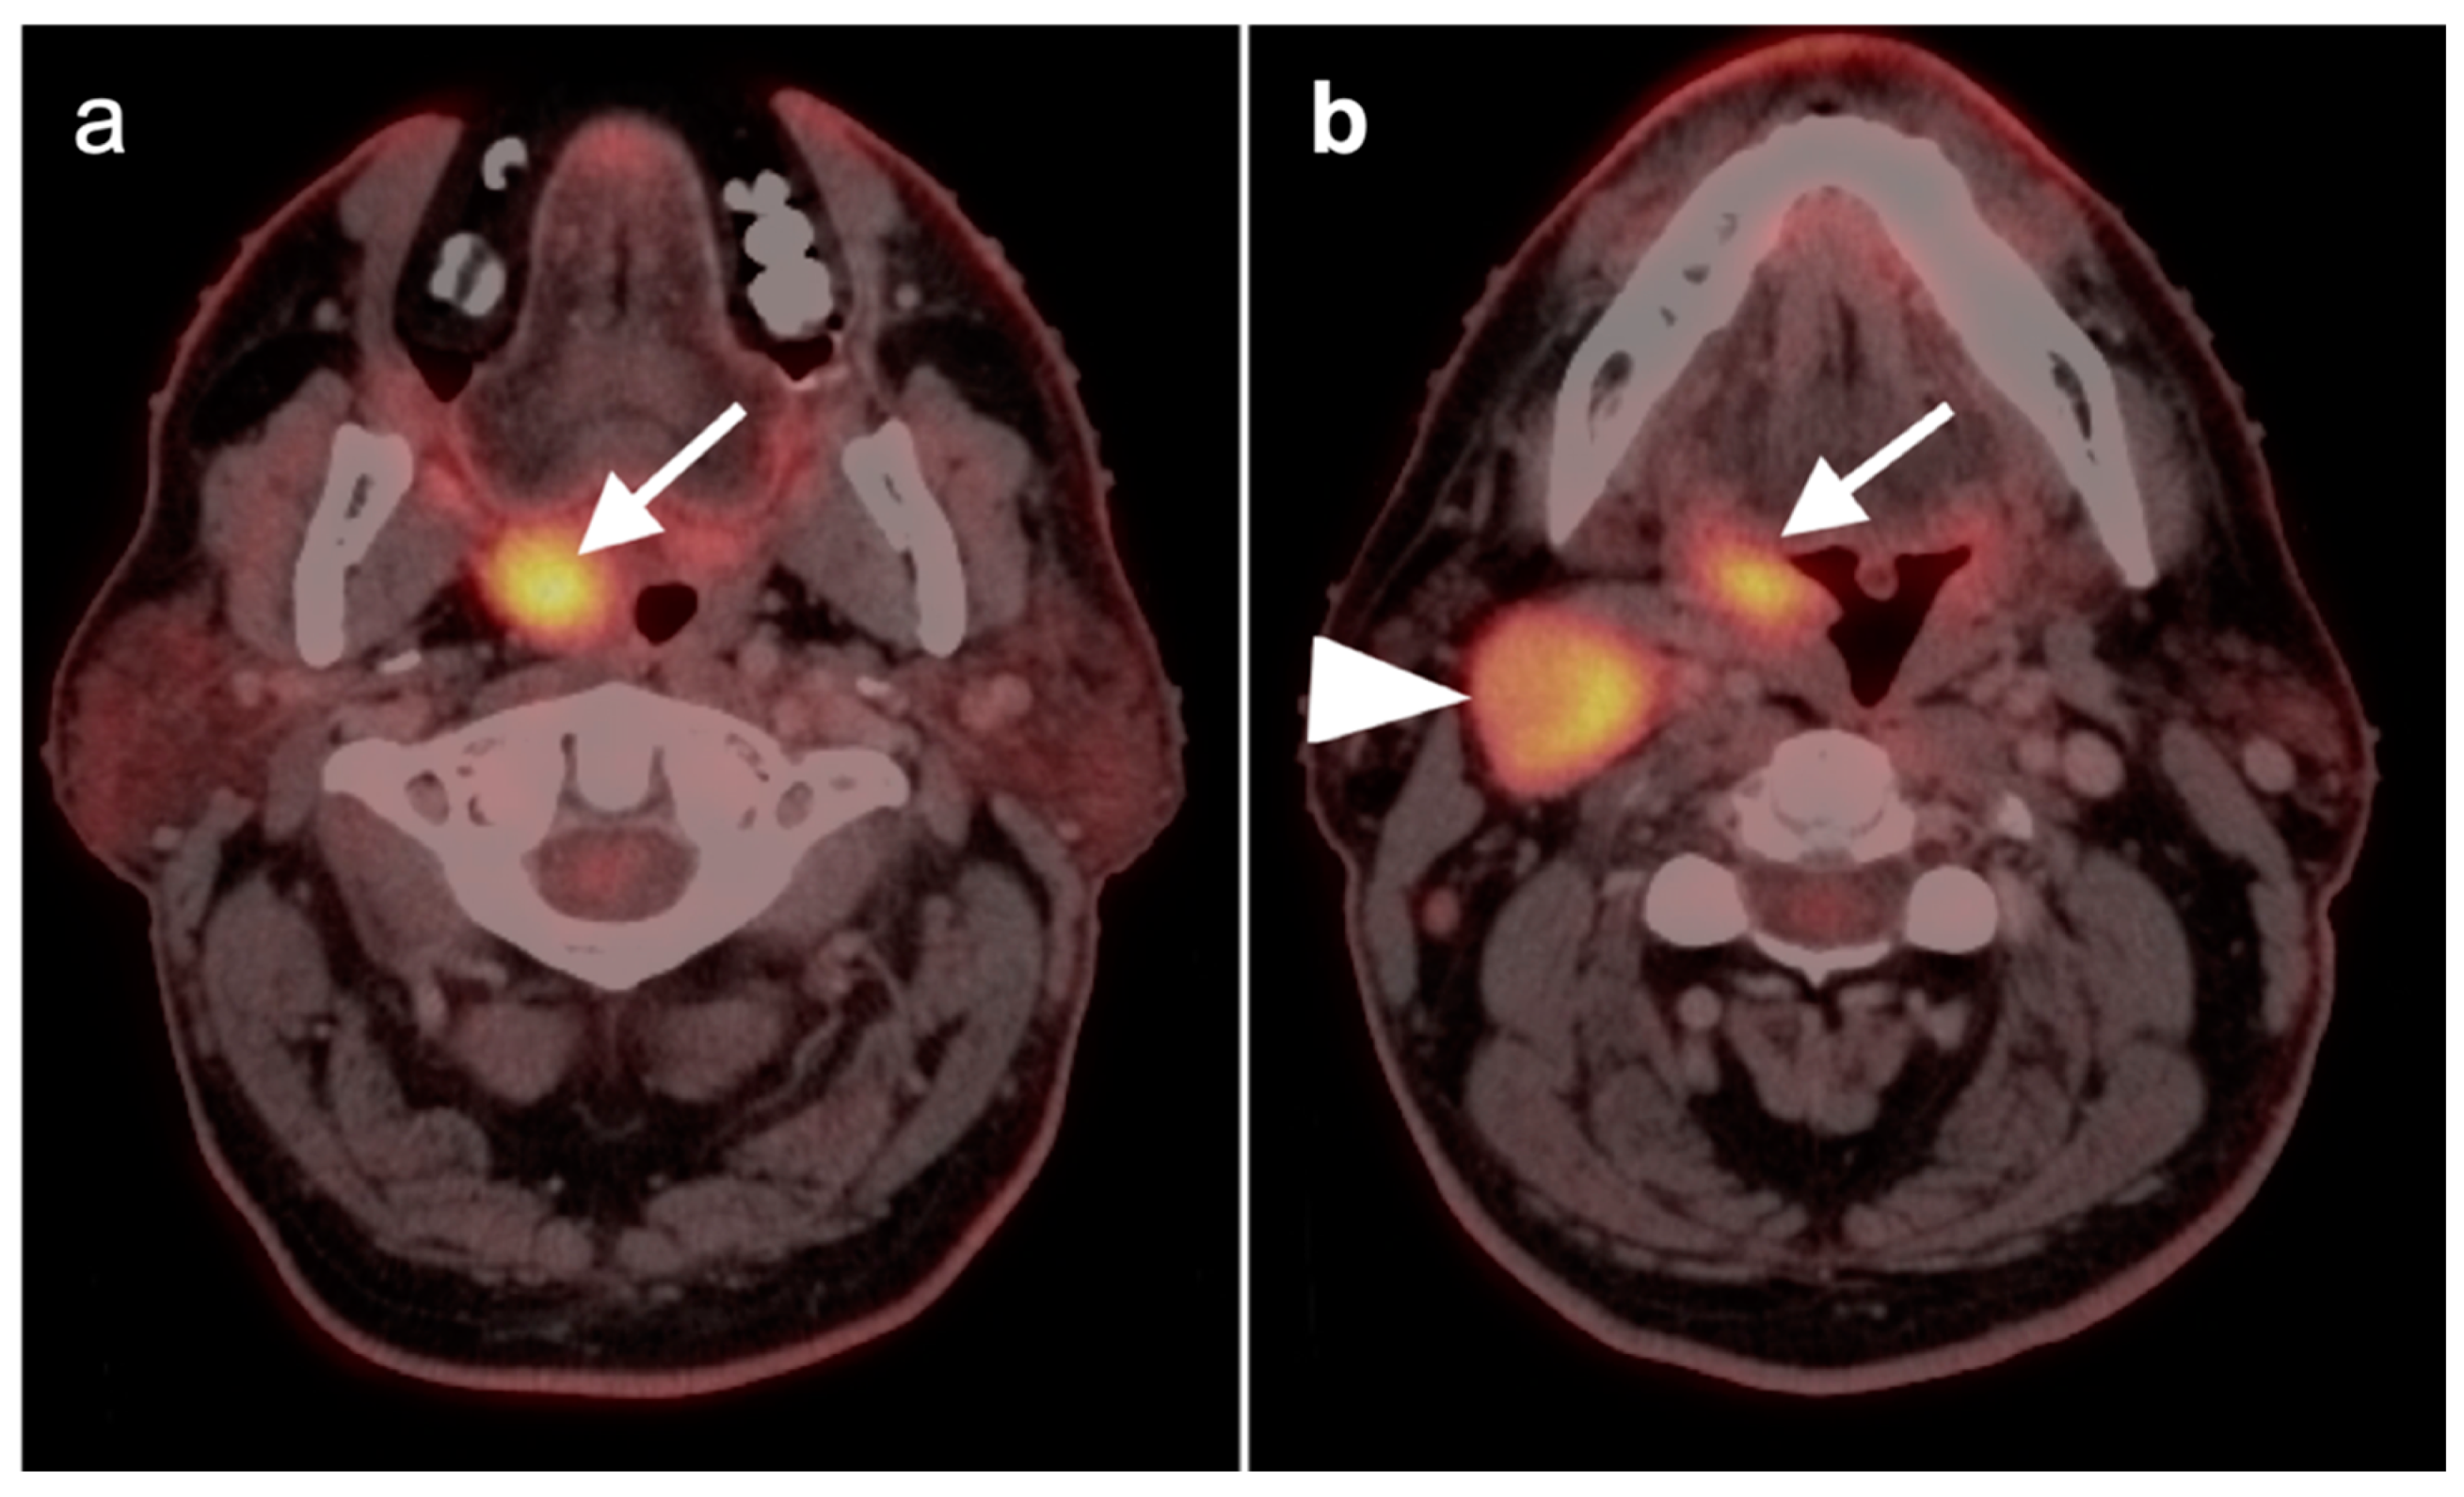

2.2. Squamous Cell Carcinoma of the Head and Neck (SCCHN)

- Oral cavity squamous cell carcinoma

- Oropharyngeal squamous cell carcinoma